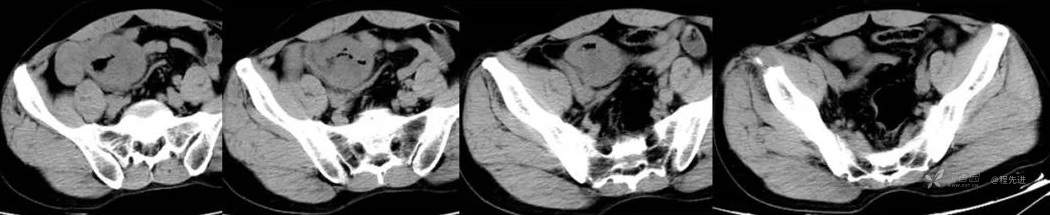

动脉期